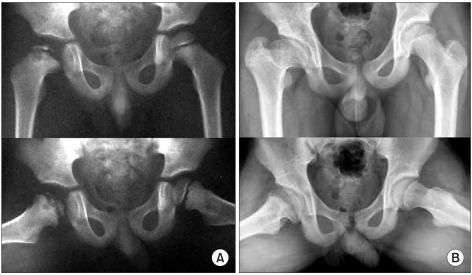

Thirty nine patients diagnosed with lateral pillar C in LCPD from May, 1977, to October, 2001 were reviewed, and their skeletal maturity was followed. The mean follow up duration was 12 years and 7 months (4 years, 6 months to 24 years, 9 months). Lateral pillar C classification was divided into C1 (50-75% collapse of the lateral pillar) and C2 (> 75%). All radiological and clinical prognostic factors were evaluated. The final results were evaluated according to the Stulberg classification.

Twenty one and 18 of the affected hips were in groups C1 and C2, respectively. According to the Stulberg classification, the final results of group C1 were better than those of C2 (p = 0.002). Patients with more head-at-risk signs had significantly poorer outcomes.

回顾 1977 年 5 月至 2001 年 10 月期间诊断为 LCPD 外侧柱 C 型的 39 例患者,并对其骨骼成熟度进行随访。平均随访时间为 12 年 7 个月(4 年 6 个月至 24 年 9 个月)。外侧柱 C 型分为 C1(外侧柱塌陷 50-75%)和 C2(>75%)。评估了所有影像学和临床预后因素。最终结果根据 Stulberg 分类进行评估。

受累髋关节中,C1 组和 C2 组分别为 21 例和 18 例。根据 Stulberg 分类,C1 组的最终结果优于 C2 组(p=0.002)。头骺受累征象较多的患者预后明显较差。